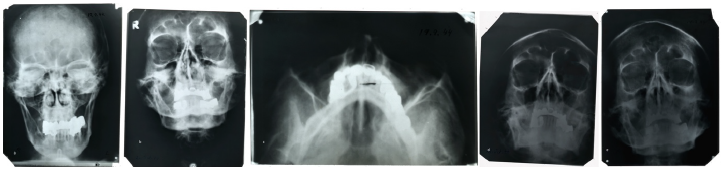

Второй образец, точнее, группа образцов из архива ФСБ (бывшего архива КГБ), представляет собой фрагмент верхней и три фрагмента нижней челюсти с зубами и коронками. Исследователи провели визуальное исследование костей и зубов под бинокуляром, элементный анализ костей и анализ поверхности зубов при помощи электронной микроскопии. Кроме того, в распоряжении экспертов оказались рентгеновские снимки головы, сделанные Гитлером в 1944 году, которые ранее хранились в США. Как видно на снимках, у него сохранилось только четыре целых собственных зуба (нижние резцы). Оказавшиеся у ученых фрагменты челюстей действительно содержали целые нижние резцы, а почти все остальные зубы были с металлическими коронками.

Рентгеновские снимки Адольфа Гитлера, сделанные в 1944 году, фото: P. Charlier et al / European Journal of Internal Medicine 2018